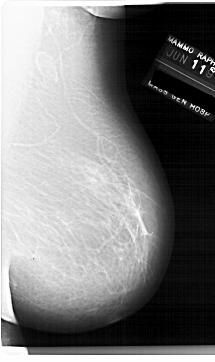

A_1920_1.LEFT_MLO

LEFT_MLO LINES 6751 PIXELS_PER_LINE 3946 BITS_PER_PIXEL 12 RESOLUTION 43.5 OVERLAY

FILE: A_1920_1.LEFT_MLO.OVERLAY

TOTAL_ABNORMALITIES 1

ABNORMALITY 1

LESION_TYPE MASS SHAPE OVAL MARGINS OBSCURED

ASSESSMENT 3

SUBTLETY 4

PATHOLOGY BENIGN

TOTAL_OUTLINES 1

BOUNDARY